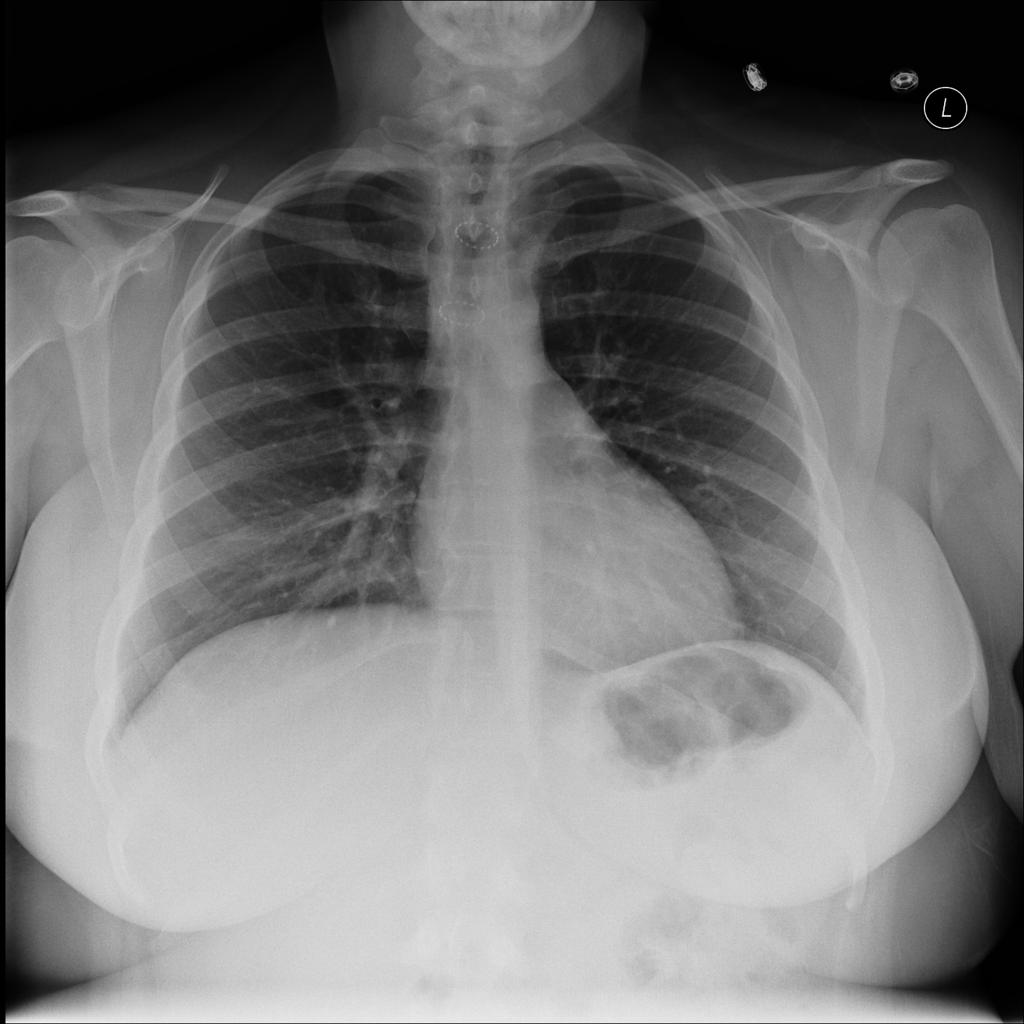

При диагностике стеноза трахеи, в основном, используется эндоскопическое и рентгенологическое исследования. Степень проходимости трахеи определяют по показаниям пневмотахографии. Нередко одышку и кашель, наблюдающиеся у больного связывают с болезнью легких, за счет чего во многих случаях стеноз трахеи диагностируется в более позднем периоде.

Стеноз трахеи и бронхов может быть острым и хроническим. Кроме того, стенозы можно разделить на интрамуральные (обусловленные поражением стенки трахеи), экстрамуральные (сдавление стенки трахеи извне). Наконец, стенозы могут быть обусловлены поражением слизистой оболочки и элементов каркаса трахеи и бронхов (компрессионный стеноз и трахеомаляция). Классификация стенозов в зависимости от их локализации приведена на рисунке ниже.

Стеноз трахеи над трахеостомической трубкой на МРТ в боковой проекции.